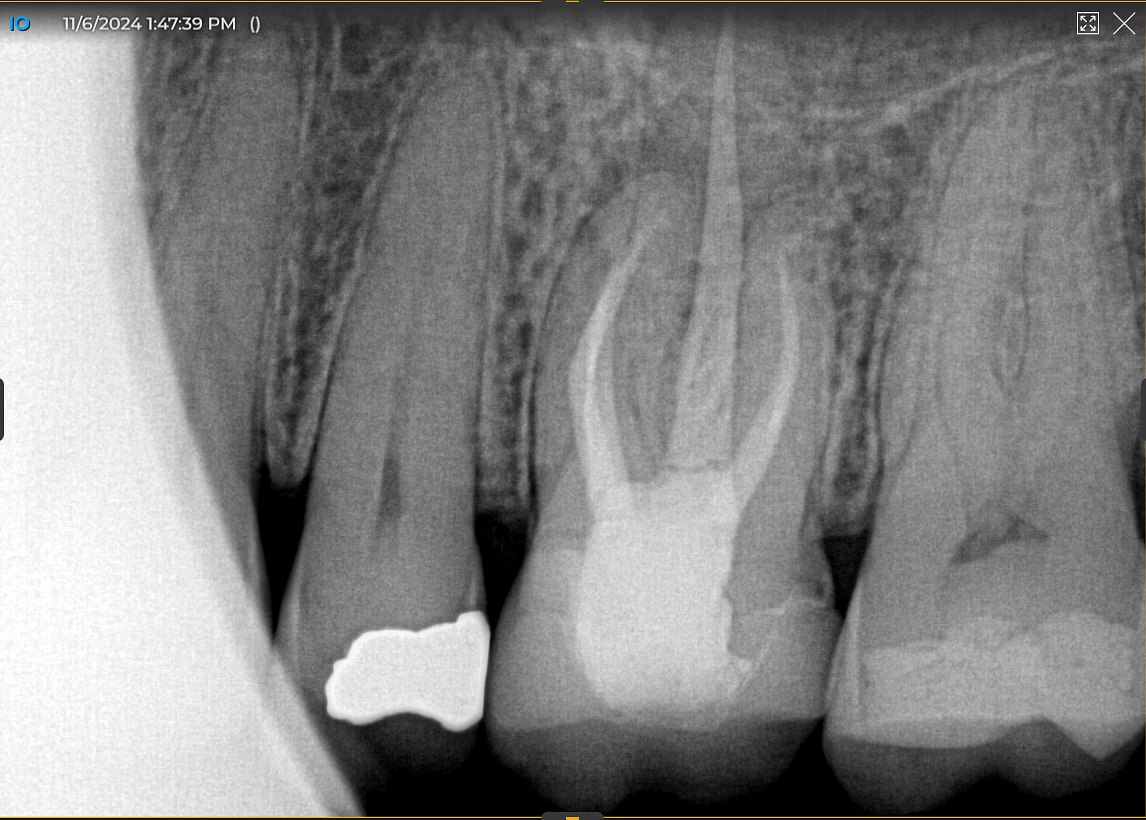

62 year old male reported last year with discomfort on the maxillary left molar region. PA x-ray showed some lesions and because we take a cone beam on everyone, we were able to see massive bone loss around all three roots that extended up into and around the sinus floor. Patient chose to have a bone graft and a future implant and his surgery was done right after the first of the year.

First, I layered a 20 × 30 collagen membrane and draped it from the buccal across to the palatal walls. Then I placed a 12 x 30 cytoplast PTFE membrane and secured both membranes with sutures. I wanted to leave the cytoplast for six weeks due to the size of the defect and graft, so I used both PTFE and glycolon sutures. The postoperative PA showed excellent bone fill that was dense.

At four months, patient returned and records were made for the implant process. Records showed good bone fill and good bone height, the implant was planned on exocad software and a guide was fabricated.